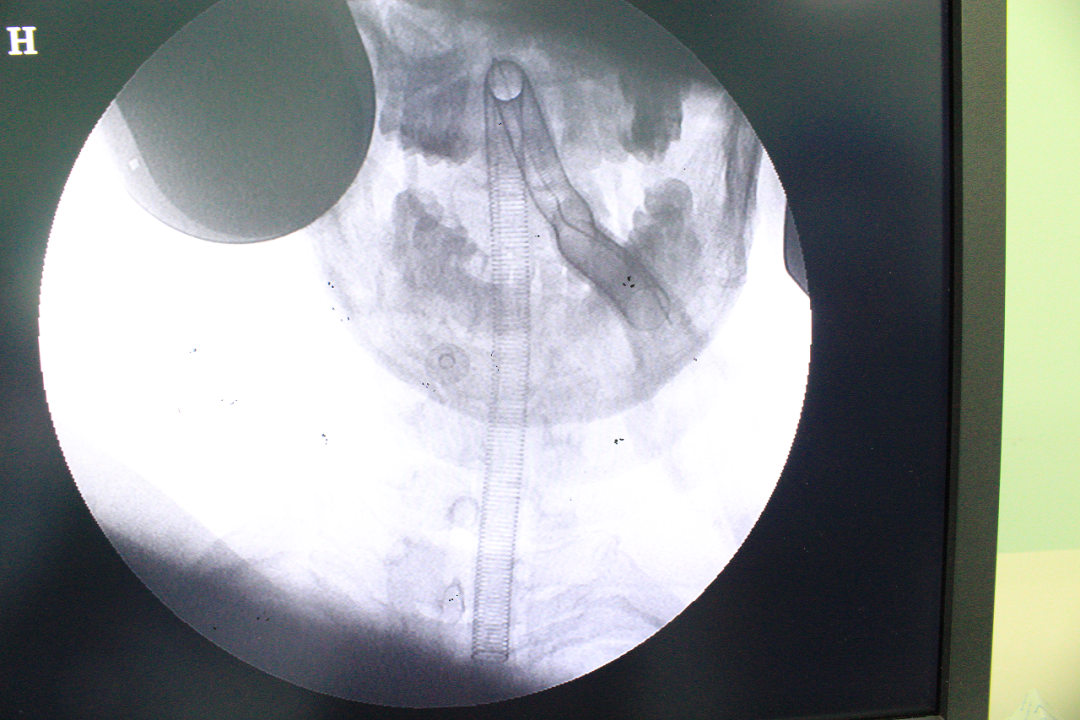

4月2日下午,白银市中心医院九病区谭庆强首席专家团队顺利完成全市首例颈5/6椎间盘突出后路经皮脊柱内镜椎间盘摘除术(KEY—HOLE技术),本例手术是继一周前ULBD术后的再一次升级。在甘肃省脊柱内镜联盟王想福主任的指导下,手术历时2小时,过程顺利,患者术前症状消失,手术获得圆满成功。

经过与甘肃省脊柱内镜专科联盟王想福主任会诊,病历典型,决定使用K—hole技术进行手术治疗。术后患者右上肢疼痛麻木缓解,术后第二天拔出引流管,患者情况稳定,已开始下地活动,正在积极康复中。